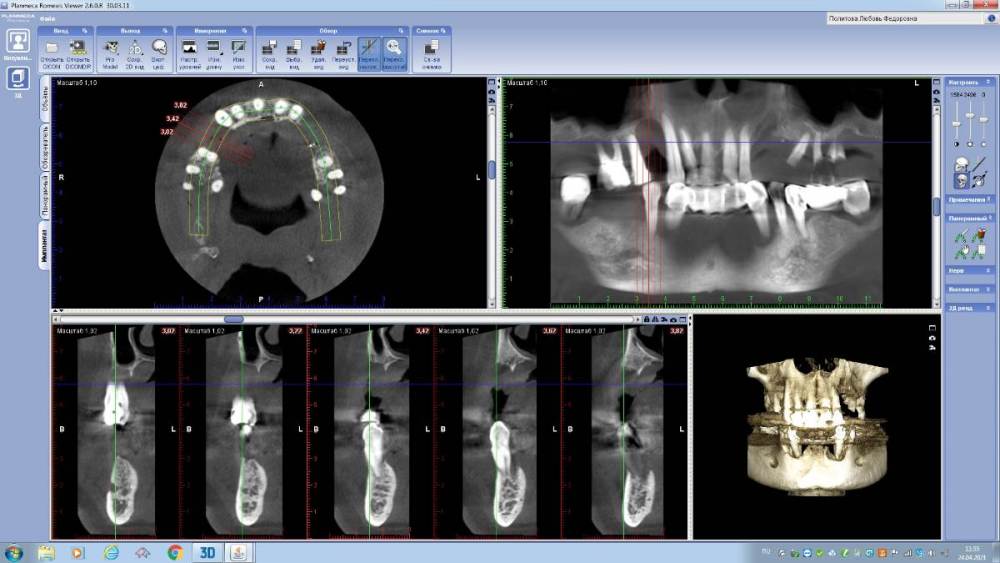

annda Опубликовано 29 апреля, 2021 Поделиться Опубликовано 29 апреля, 2021 (изменено) Интересующая область-14. Пациентка обратилась для протезирования дефектов полости рта.Было предложено удалить весь верх и низ.На верху было предложено все на 6,внизу все на 4х,но решила сделать все на 5(а вот так вот). Поступил категорический отказ удалять верхние передние зубы(на приеме подвижность 1-2й степени).Тогда как альтернатива предложен съемник на локаторах как временный вариант(с тайной мыслью-"вот поносишь и все равно придешь за первым вариантом") На операции одномоментное удаление боковых верхних и низа,установка имплантатов,формики и нагрузка в соответствии с торками.Дикий дефект в области 14 просто откюретажили до костной ткани,грануляции вырезали. Через 4 месяца приносит новую КТ.Я просто онемела.Зубы на верхней челюсти неподвижны от слова совсем...Вот что это было и есть?? Изменено 29 апреля, 2021 пользователем annda 1 Ссылка на комментарий

Дмитрий Л. Опубликовано 29 апреля, 2021 Поделиться Опубликовано 29 апреля, 2021 Не могу поверить...) разные срезы или настройки кт. Ссылка на комментарий

annda Опубликовано 29 апреля, 2021 Автор Поделиться Опубликовано 29 апреля, 2021 По протезке не было ничего, от слова совсем. Даже кривые настройки КТ не могут так исказить картину:))Срезы одни и те же , видны на обоих снимках, зубы центральные принадлежат одному человеку. Кстати, 68 лет от роду... Кость уже пощупала фрезой, абсолютно полноценная костяка... Ссылка на комментарий